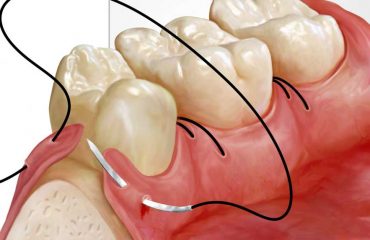

جراحی لثه به صورت کلی بر اساس علل مختلف با دو روش انجام می شود که عبارتند از: جراحی معمولی و جراحی لثه با لیزر.

جراحی لثه به واسطه لیزر در واقع به گونه ای است که در آن برای جراحی از دستگاه لیزر استفاده می شود و جراحت های مورد نیاز در لثه توسط لیزر انجام می شوند. این روش از مزایای زیادی برخوردار است و جدیدترین روش جراحی لثه است که پزشکان از آن استقبال خوبی کرده اند.

- ایجاد جراحت های کمتر در لثه

- کاهش درد و خونریزی و درد در لثه

- عدم نیاز به بخیه زدن لثه به دلیل کاهش جراحت ها

- عدم آسیب دیدن بافت های مجاور